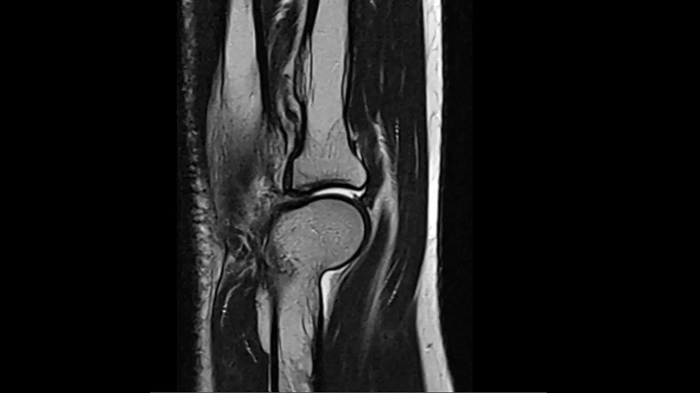

Elbow

T2 TSE with Deep Resolve

Exceptional performance for small joints owing to Deep Resolve.

Deep Resolve Gain & Sharp

0.3 x 0.3 x 3.0 mm2

TA 2:54 minutes

MAC-ID: 7aaaa0190. Image Credit: Siemens Healthineers

T1 TSE with Deep Resolve

Thanks to Simultaneous Multi-Slice and Deep Resolve, an exceptional performance for small joints is possible.

SMS 2 | Deep Resolve Gain & Sharp

0.3 x 0.3 x 3.0 mm2

TA 2:15 minutes

MAC-ID: 7aaaa0190. Image Credit: Siemens Healthineers

PD TSE Fat Sat with Deep Resolve

Thanks to Deep Resolve, outstanding performance for small joints is possible.

Deep Resolve Gain & Sharp

0.3 x 0.3 x 3.0 mm2

TA 3:43 minutes

MAC-ID: 7aaaa0190. Image Credit: Siemens Healthineers